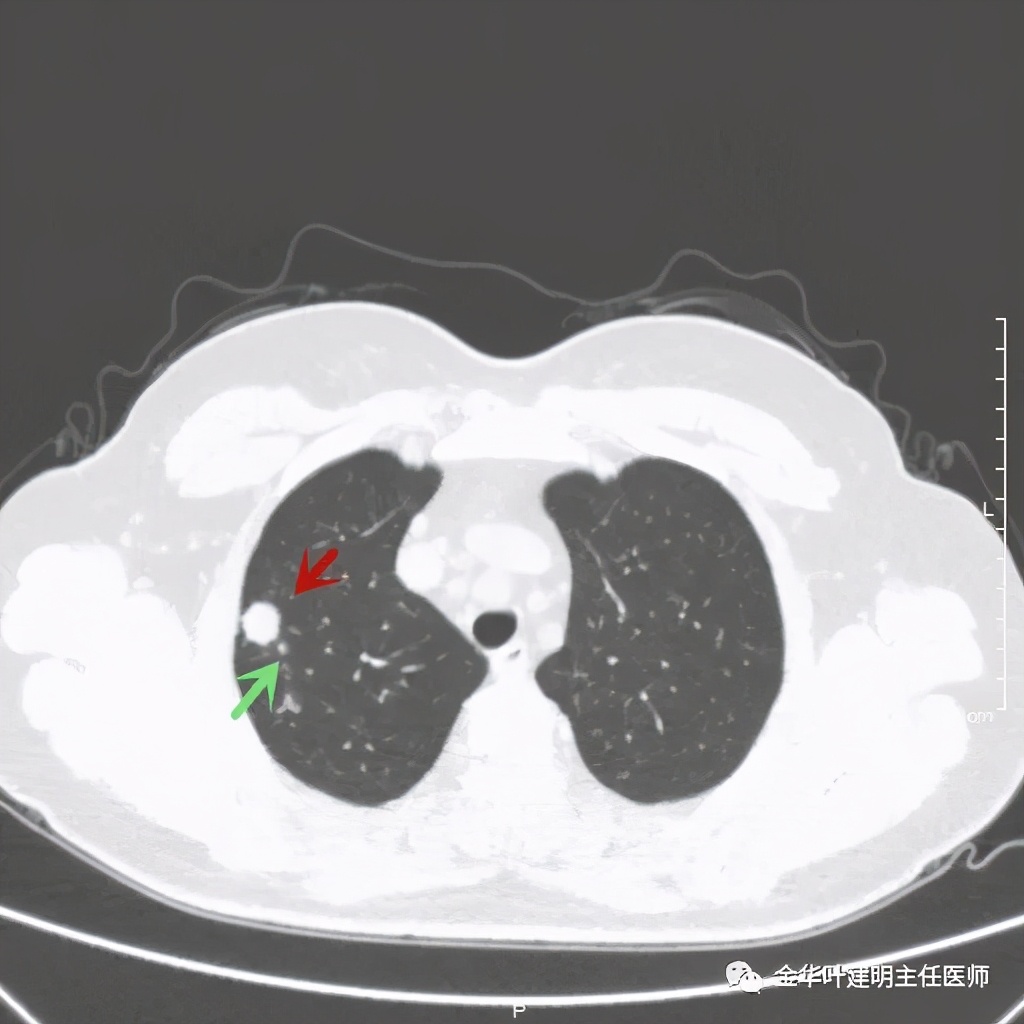

病灶比较光滑,密度高,旁边有小的卫星灶,不清爽

绿色箭头示主病灶边有小的实性微小结节,主病灶边缘非常光滑,没有毛刺、分叶等征